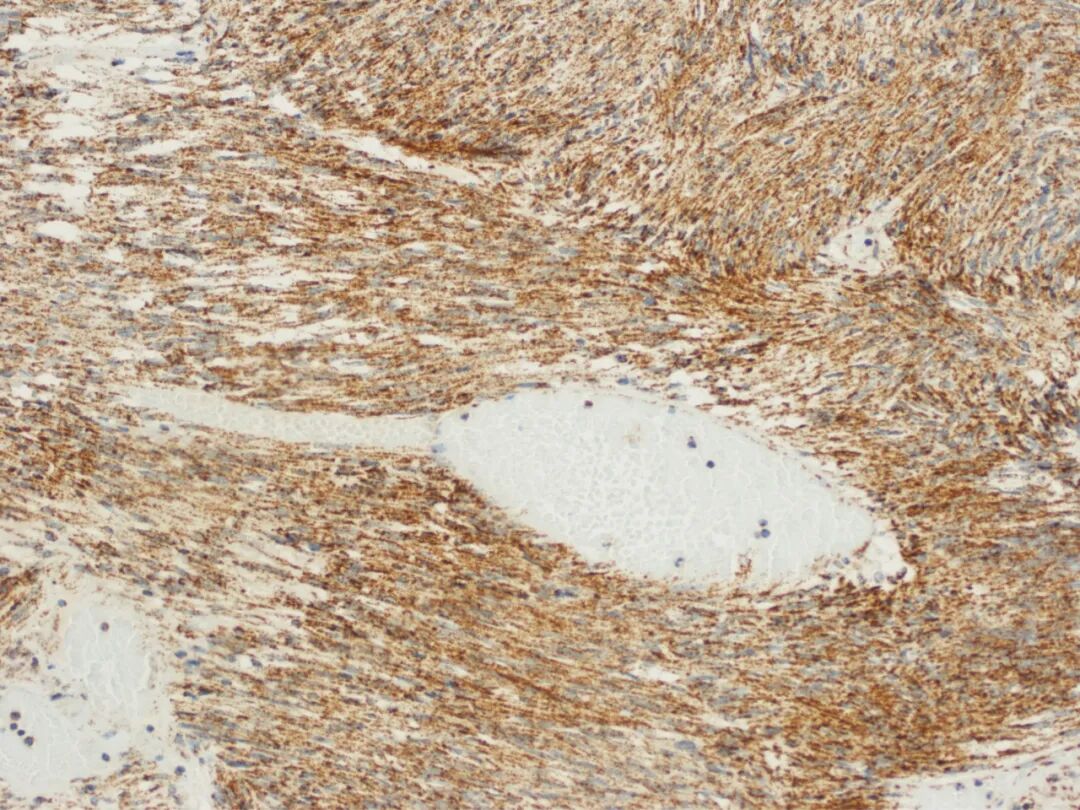

图1. 副神经节瘤肿瘤细胞缺失表达(SDHB 阴性)